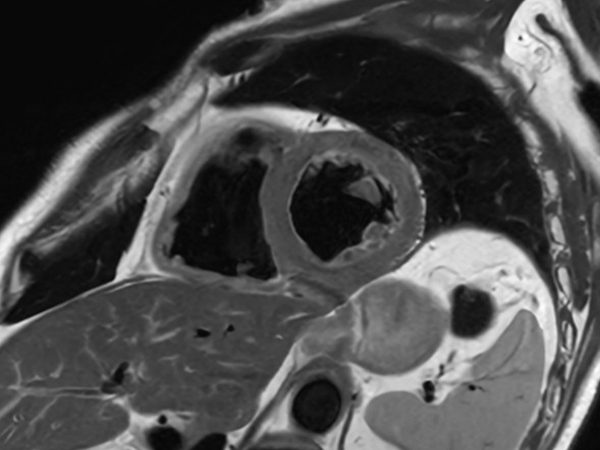

Comprehensive Cardiac with SmartSpeed Precise